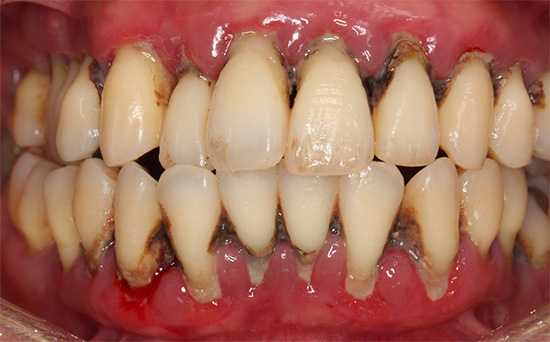

治療終了後7年経過した口腔内写真

治療終了時

歯周病による感染や炎症をブラッシングと歯周病治療を行い、動揺する歯を固定して機能の回復を行った。この治療は、患者さんのブラッシングが十分でないと、逆に進行してしまい、また精度の高いブリッジを作らないと、早期に再治療や最悪、抜歯になってしまう可能性がある。

幸い、この患者さんは非常に治療に協力していただき、また3ヶ月ごとに来院してチェックとクリーニングをお手伝いしている。

治療費の合計 およそ90万円

治療期間 およそ10ヶ月